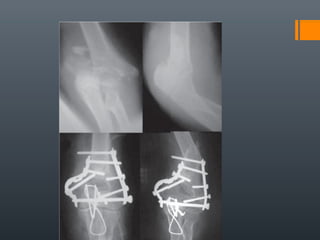

LUXACIONES Y

FRACTURAS DEL CODOCLASIFICACIÓN

A.D. DELGADO MARTINEZ. Cirugía Ortopédica y Traumatología. Madrid: Panamericana, 2009.